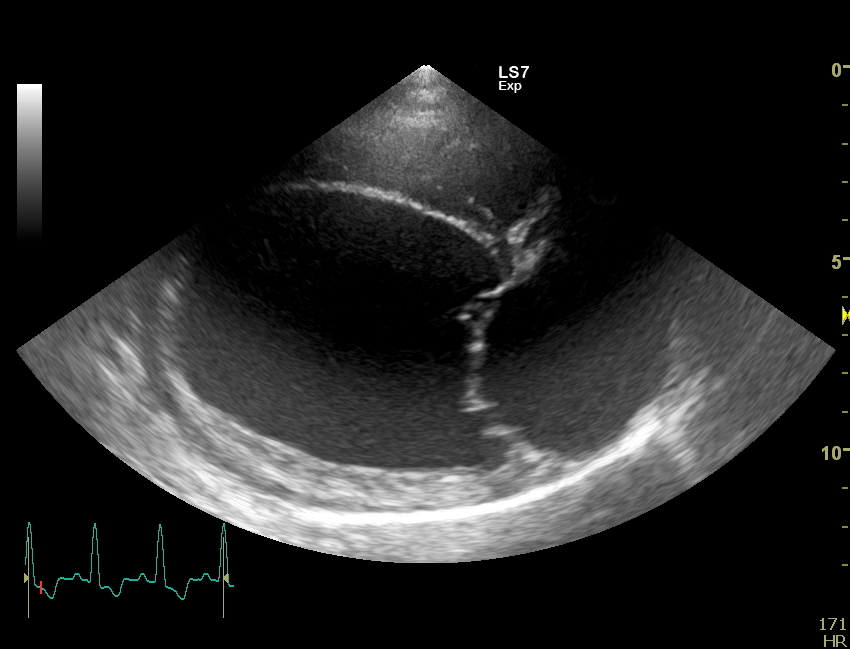

Weitergehend haben wir dann eine Herzultraschalluntersuchung durchgeführt um weitere Informationen über die zugrundeliegende Erkrankung zu bekommen. Auch in der Echokardiografie stellte sich das Herz deutlich zu groß da. Die linke Hauptkammer und der linke Vorhof sind massiv volumenüberladen, also mit zu viel Blut gefüllt. Durch die starke Blutfülle im Herzen hat sich auch der Klappenapparat der Mitralklappe aufgedehnt, sodass dieses Rückschlagsventil zwischen der linken Kammer und dem linken Vorhof nicht mehr richtig abdichtet. Resultat ist eine Mitralklappeninsuffizienz, die bei jedem Herzschlag etwas Blut in den linken Vorhof zurückfließen lässt. Der linke Vorhof wird, wie hier bei Faust sehr groß und das Blut staut in den Lungenkreislauf zurück, es entsteht ein Lungenödem. Vereinfacht gesagt Faust hat „Wasser auf der Lunge“, eine weitere wichtige Ursache für Husten bei unseren herzkranken Hunden. Die Herzmuskulatur bei Faust ist eher dünn und die Pumpkraft (Kontraktilität) der Herzmuskulatur ist sehr schwach.

Daraus leitet sich die Diagnose ab: Faust hat eine dilatative Cardiomyopathie, DCM.